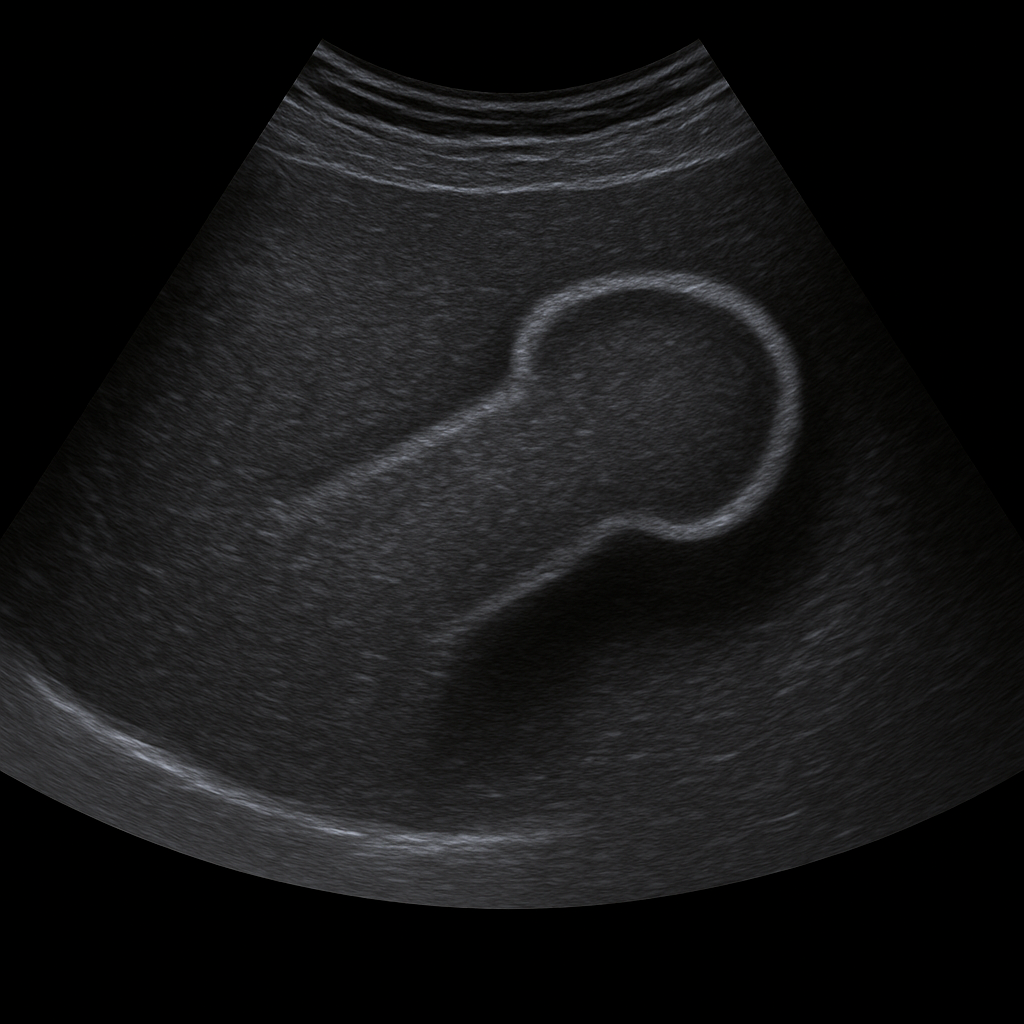

- Ultrasound of the penis shows vascular flow, tissue changes and scarring in the penis shaft.

- Recommended for pain, swelling, trauma or bending (curvature).

- Quick, painless and radiation-free examination of corpora cavernosa and blood vessels.

- Written opinion and recommendation from a specialist doctor included.